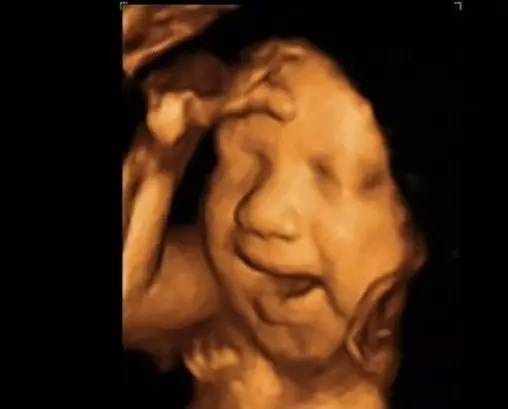

第二次早孕期超声检查(孕11-13+6孕周NT检查):建议选择四维彩超检查。此期主要进行遗传学超声检查以筛查胎儿染色体异常高危人群,重点测量胎儿颈项部透明层(NT)、鼻骨等;同时可检出一些大体结构畸形,如无脑儿、连体双胎等。

第三次中孕期系统超声筛查(孕22-24周):建议选择四维彩超检查 。此期胎儿各器官基本发育,羊水量适中,超声图像清晰,是胎儿畸形筛查最佳时间,大部分胎儿结构异常可在这个阶段检出。